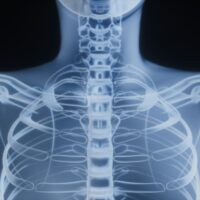

Thoracic Spine Fractures After a Car Accident: Mid-Back Injuries With Serious and Lasting Consequences

Thoracic spine fractures are serious car accident injuries involving the middle portion of the spine, which plays a critical role in protecting the spinal cord and supporting the upper body. Although thoracic vertebrae are more rigid than the cervical or lumbar spine, the force generated in motor vehicle collisions across Virginia, Maryland, and Washington,… Read More »